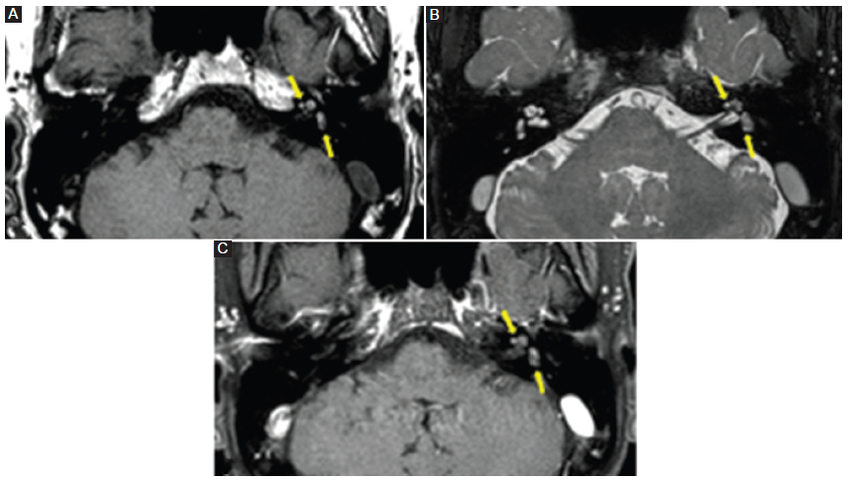

Todos los pacientes con neurinoma intralaberíntico revelaban una baja señal en la secuencia T2 AR, ligera hiperseñal en la secuencia T1 SC y realce poscontraste con márgenes bien definidos (Fig. 3). Tres pacientes con laberintitis inflamatoria (42,5%) mostraron baja señal en las secuencias T2 AR y T1 SC, y 5 pacientes (71%) manifestaban realce con el contraste (Fig. 4), con márgenes menos claros que los pacientes con neurinoma. Los 5 pacientes con laberintitis osificante presentaron baja señal en la secuencia T2 AR, y 2 pacientes (40%) tenían hiperseñal en la secuencia T1 SC (Fig. 5). Solo en 3 pacientes con laberintitis osificante se realizó secuencia con contraste, y 2 de ellos mostraron realce. Los 3 pacientes con hemorragia evidenciaron una señal alta en la secuencia sin contraste (Fig. 6) y 2 (66,7%) presentaron refuerzo poscontraste (Tabla 2).

En los pacientes analizados en nuestra investigación, el 100% presentaron las tres características clásicas mencionadas en la literatura: alta señal en la secuencia sin contraste, ausencia de señal en la secuencia T2 AR y marcado realce con el contraste5,6.